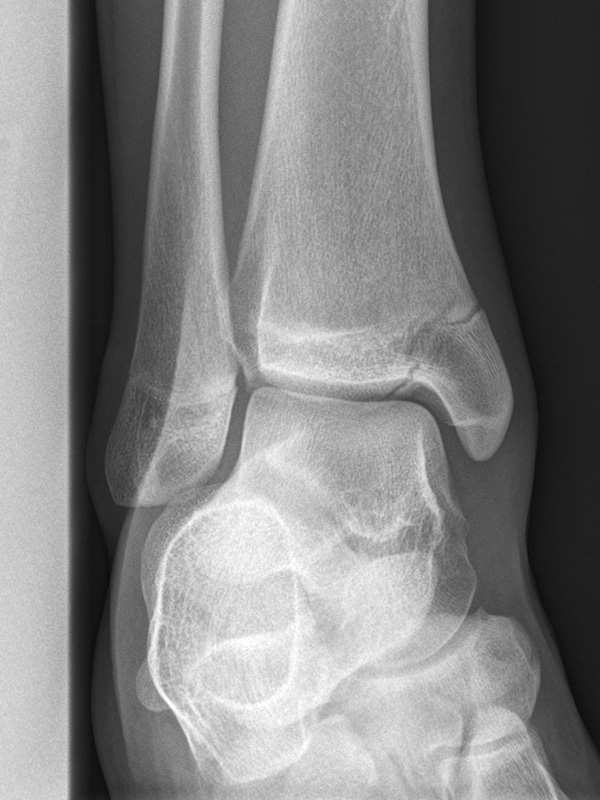

Sprunggelenk Mortise-Aufnahme mit Belastung

Positionierung:

• Der Patient steht, beide Beine sind geleichmäßig belastet.

• Der Fuß wird um ca. 20° innenrotiert. Der Zentralstrahl ist mittig auf den Gelenkspalt des oberen Sprunggelenks ausgerichtet.

• Die Röntgenkassette liegt dem Fuß dorsal an.

Kennzeichen des Röntgenbildes:

• Überlagerungsfreie Darstellung des Talus und der Malleolengabel.

• Der Gelenksspalt zwischen Talus und Fibula sowie zwischen Talus und Innenknöchel zeigt eine identische Breite.

• Der Weichteilmantel ist erkennbar.

Besondere Bemerkungen zum Beispielbild:

• Zustand nach Fremdkörperverletzung.

• Die röntgendichte Struktur (Metall) befindet sich im Bereich der lateralen Kalkaneuswand.

Zur Vollansicht und zum Lesen der Bildbeschreibung bitte die Bilder anklicken.